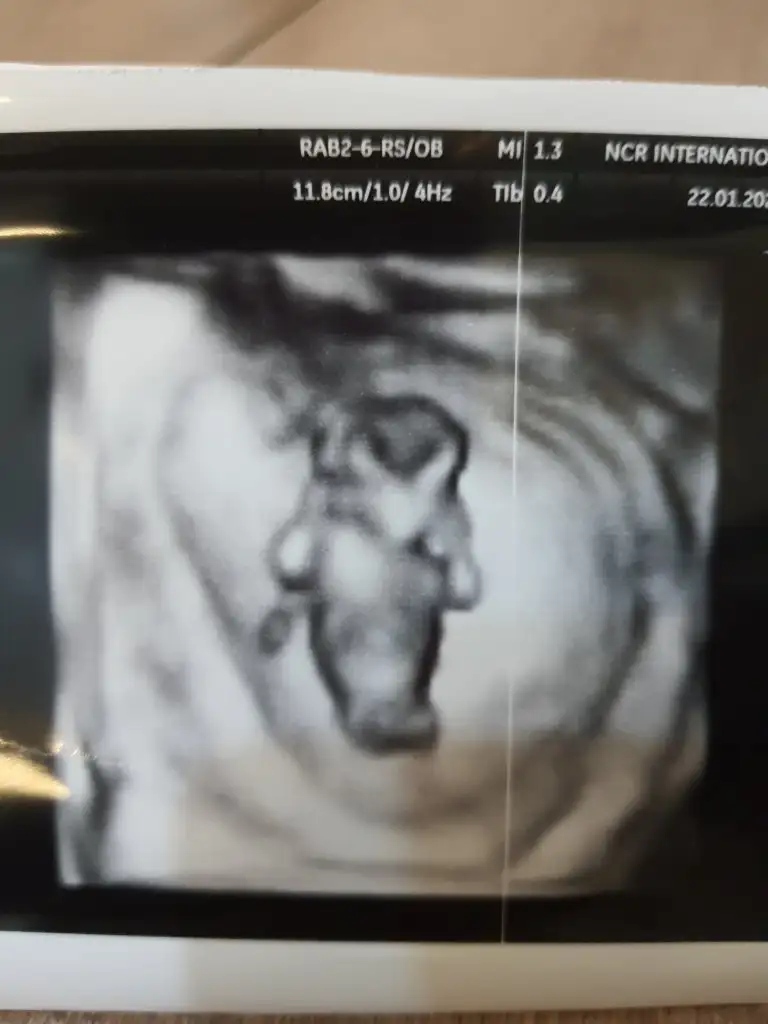

Ikra meyra Ikra meyra canim meraba 12+1 doktorum %80 tahminde bulundu ama sana da sormak istedim bi bakarmisin şimdiden tsk ederim 😇🥰

16114342874286929225332790290193.webp

• 20210122_212620.webp

20210122_212620.webp

18,5 KB · Görüntüleme: 76

• 20210122_212608.webp

20210122_212608.webp

22,4 KB · Görüntüleme: 59

• 20210122_212559.webp

20210122_212559.webp

26 KB · Görüntüleme: 73

Banada tahminde bulunur musunuz ? ben hiç bir şey anlamadım :110:

11+3 burda